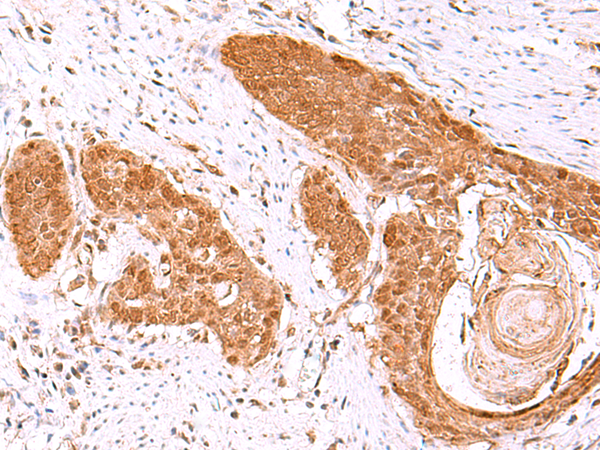

分类: 科研抗体货号: P10149别名: FPS; FPPS; POROK9应用: IHC反应种属: Human, Mouse, Rat